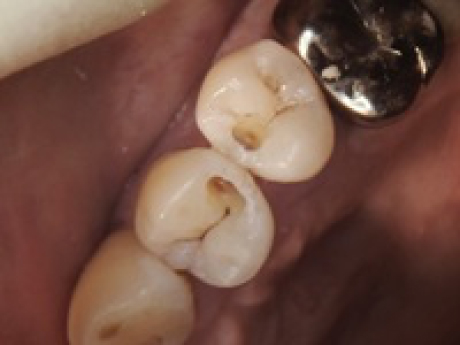

case1